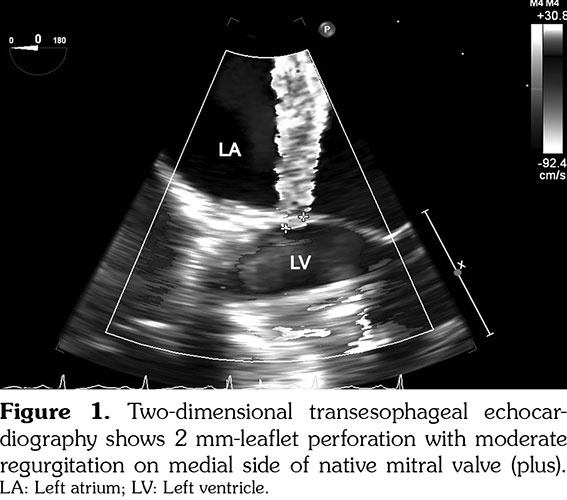

A 26-year-old female patient with eight-year history of TA had undergone Bentall procedure involving composite replacements of aortic root with 30 mm Dacron tube graft and St. Jude, No. 23 mechanical aortic valve (St. Jude Medical Drive. St. Paul, Minnesota, USA) due to severe aortic aneurysm and valve regurgitation seven years ago and presented with chest pain and labile hypertension. She was treated with combined immunosuppressive therapy of prednisolone and azathioprine for five years. Additionally, the patient was on warfarin treatment with a target international normalized ratio between 2-4 for prosthetic aortic valve replacement. On physical examination, she had rhythmic heart beats, 3/6 systolic murmur on the fifth left intercostal space. Her blood pressure on the right arm was 150/96 mmHg and there was no pressure difference between her right arm and legs. Routine blood tests showed that inflammatory markers and white blood cell counts were within normal limits and two blood culture sets taken on admission were negative. Electrocardiography revealed a normal sinus rhythm with a ventricular rate of 75 beats/minute. Comprehensive transthoracic and real-time two- and three-dimensional transesophageal echocardiography showed 2 mm-anterior leaflet perforation with moderate regurgitation on medial side of native mitral valve as well as normal left ventricular function and wall motion, and functionally normal aortic root replacement with mechanical composite aortic valve (Figure 1). There was no annular calcification, and no valvular vegetations were seen. Three-dimensional thoracoabdominal computed tomography revealed aneurysm and coarctation of aorta with diffuse calcifications on the descending aorta (Figure 2). Conventional aortography was performed using a pigtail catheter which revealed an aortic gradient of 15-20 mmHg. Since there was no significant hemodynamic gradient and moderately mitral valve regurgitation, medical treatment was advised. Written informed consent was obtained from the patient.